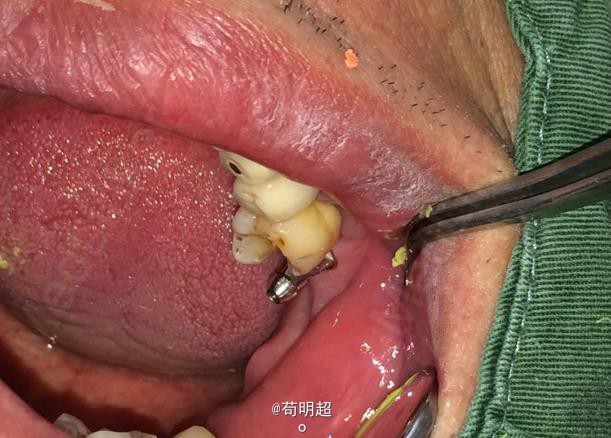

47牙齿种植修复

患者,男,40岁,47牙缺失要求种植。平素体质一般,无药物、食物过敏史,无高血压、心脏病等系统病史。

患者满意,效果很好。